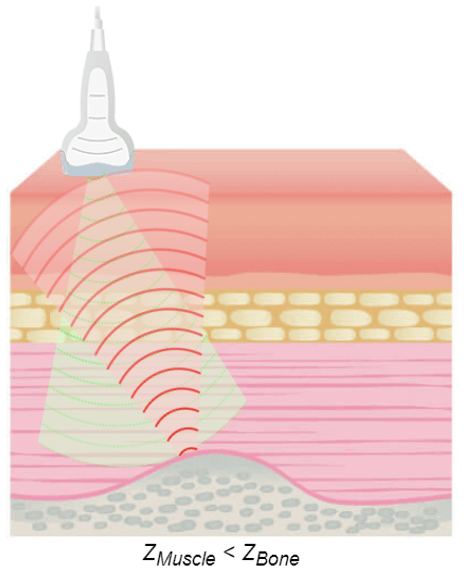

The greater the difference in acoustic impedance between two adjacent tissues, the more ultrasound energy will be reflected at the boundary. The acoustic shadow occurs when the sound wave meets a very dense structure. Almost all the sound is reflected, resulting in an acoustic shadow. Shading can occur due to intense reflectors such as calcification, air, or bone.

Some artifacts have their origin in a wrong setting of the device. For example, an excessive level of amplification may reveal scattered echoes in a fluid-structure (bladder, artery) corresponding to an exaggerated amplification of the noise. Other artifacts are related to the nature of the interactions between ultrasound and tissue. We can mention these 4 main artifacts: The acoustic shade, the posterior strengthening, the reverberation, and the mirror imaging.

Acoustic Shade

The acoustic shadow phenomenon occurs whenever the ultrasonic beam is intercepted by a highly reflective structure. This is the case of bones, digestive gases, kidney stones, or gallstones. In this image, the reflecting wall is represented by a very intense echo behind, which is projected in a cone of acoustic shadow where no image is visible. This artifact aids in the identification of calculi and also prevents the examination of deeper structures.